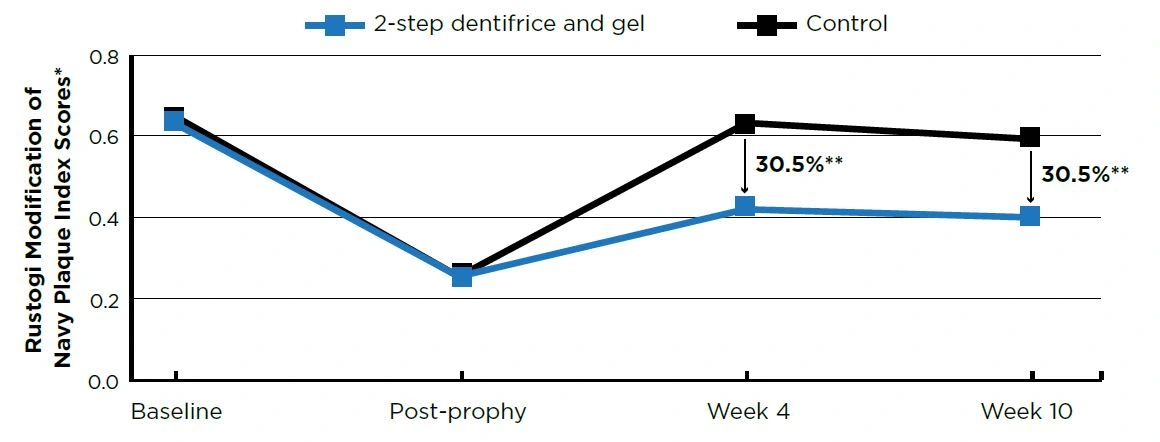

After 10 weeks of twice daily use, the 2-step dentifrice and gel system exhibited statistically lower (P<0.001) percent accumulations versus the control group in tooth stain (73.4%), plaque (30.5%), and calculus (58.6%). See Figures 1–3.

Figure 2. Plaque Scores

Figure 2. Plaque Scores

** Baseline and post-prophy scores are means; Week 4 and Week 10 scores are adjusted means. ** P<0.0001

To assess the effectiveness of a daily 2-step dentifrice and gel system to prevent the formation of stain, calculus and plaque after a dental prophylaxis.

METHODS

This was a randomized, controlled, examiner-blind, 2-treatment parallel group study. Forty-eight healthy adult volunteers with evidence of plaque and either stain or calculus completed the trial.

Following a whole-mouth dental prophylaxis, subjects were randomized to one of two groups:

- Negative control - 0.76% sodium monofluorophosphate dentifrice (Colgate® Cavity Protection, Colgate-Palmolive)

- Daily 2-step dentifrice and gel system (Crest® PRO-HEALTH™ [HD]™) - Step 1, 0.454% stannous fluoride dentifrice; Step 2, 3% hydrogen peroxide whitening gel

Both groups brushed twice daily with a soft manual toothbrush (Oral-B® Indicator™, Procter & Gamble).

Stain (Lobene Index1), calculus (Volpe-Manhold Index2) and plaque (Rustogi Modification of the Navy Plaque Index3) were measured clinically prior to receiving a dental prophylaxis, immediately after a dental prophylaxis, and after 4 and 10 weeks of product use.